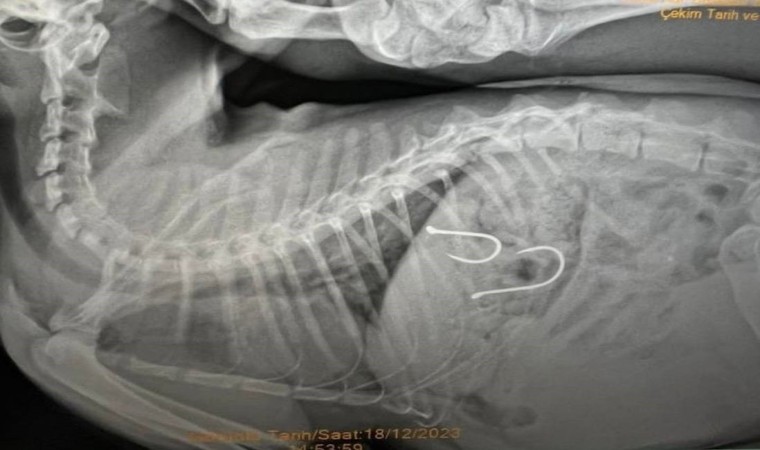

Sahil bandında dolaşan vatandaşlar, bir kedinin ağzından olta misinası sarktığını fark edince durumu Balıkesir Büyükşehir Belediyesi Sokak Hayvanları Tedavi Merkezi’ne ihbar etmişlerdi. Gelen ihbar üzerine kedi, ekipler tarafından müşahede altına alınmış ve sağlık durumu kritik olan yaralı hayvana acil olarak müdahale edilmişti. Çekilen röntgen sonucunda olta iğnelerinin kedinin midesine saplandığı anlaşılmış ve sonrasında ise kedi ameliyata alınmıştı.

Kedinin sağlık durumu ile ilgili Balıkesir Büyükşehir Belediyesi Sokak Hayvanları Tedavi Merkezi’nden edinilen son bilgilere göre, 2 adet olta iğnesi ve misinasının kedinin midesinden başarılı bir operasyonla çıkarıldığı, olta kancasının enfeksiyon oluşturma riskine karşı, antibiyotik ve serum tedavisine başlandığı belirtildi. Kedinin genel sağlık durumunda şu an için bir olumsuzluğun söz konusu olmadığı ve 48 saat yoğun bakımda tutulacağı aktarıldı.